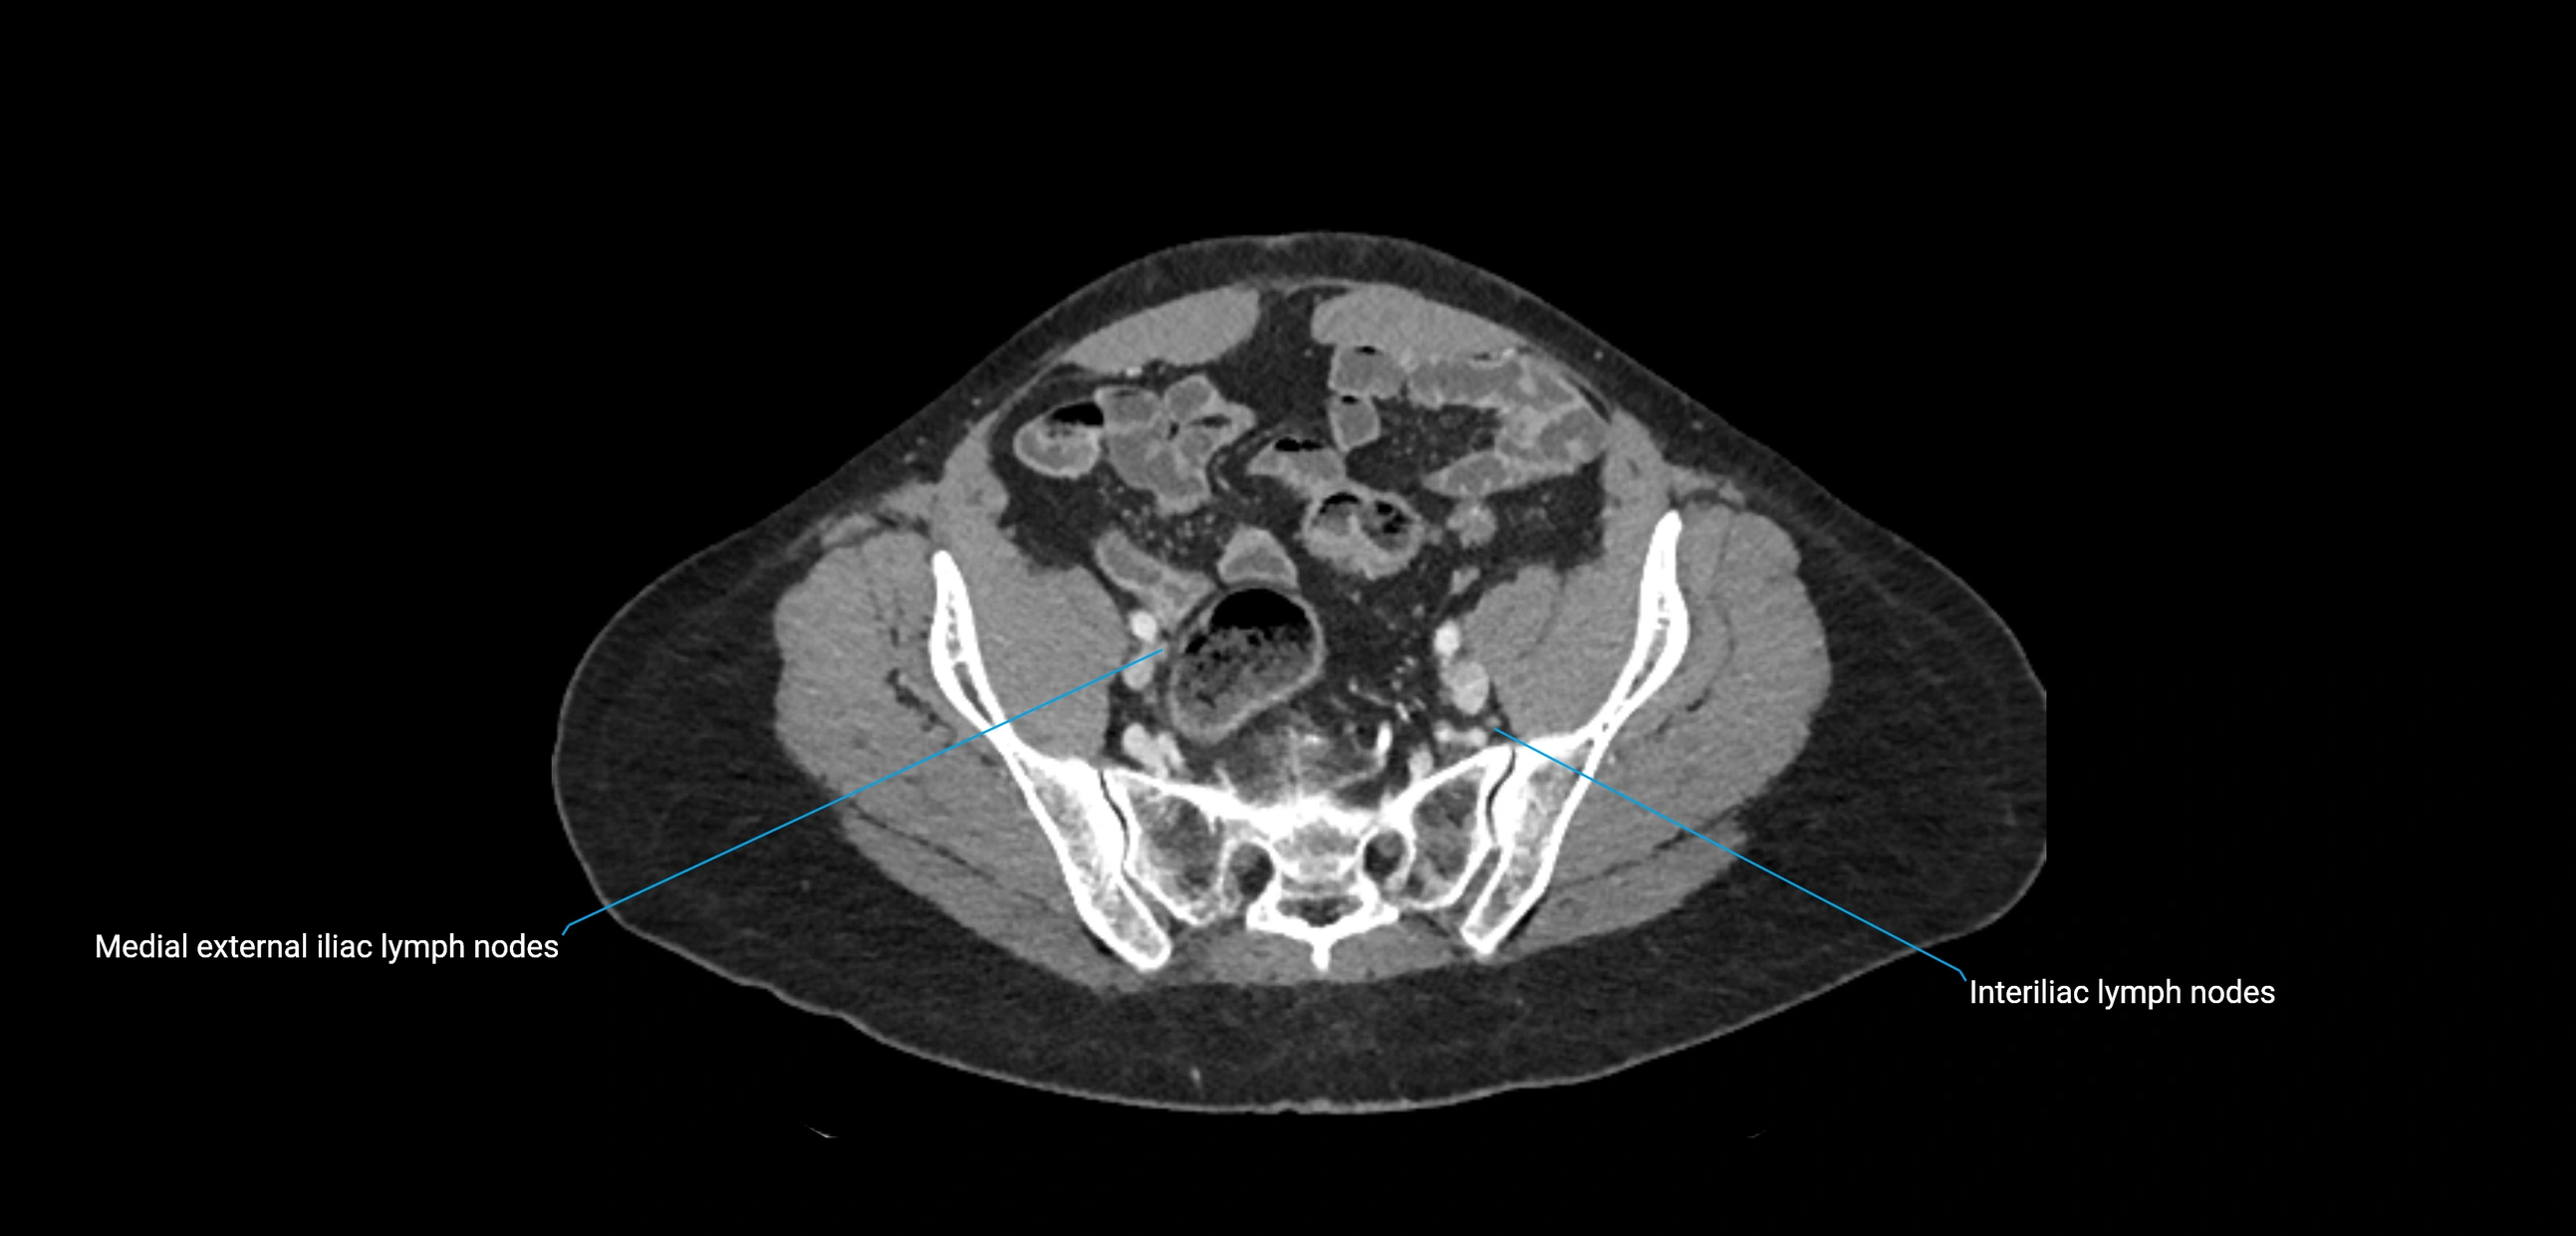

CT Appearance

CT Pre-Contrast:

• Nodes appear as soft-tissue density nodules adjacent to the aorta and IVC

• Calcification may be seen in chronic infections (e.g., tuberculosis)

CT Post-Contrast:

• Normal nodes enhance homogeneously

• Malignant nodes may show heterogeneous enhancement, central necrosis, or conglomerate formation

• Size >1 cm short axis is suspicious, though morphology and distribution are equally important